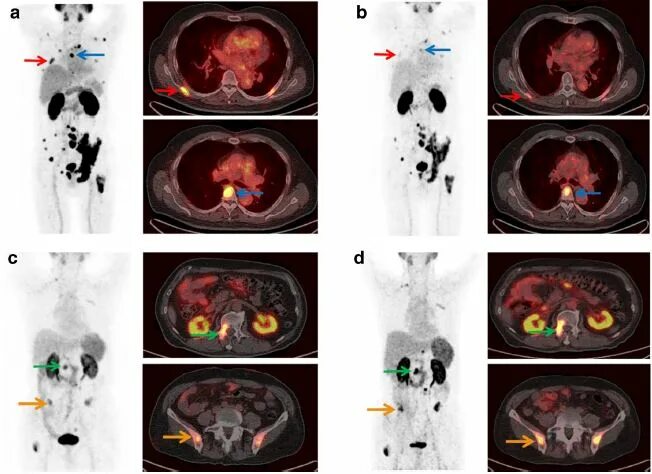

Пэт псма что это